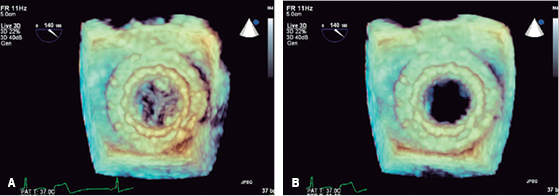

Transthoracic and transesophageal echocardiography: left ventricular end-diastolic volume of 45 milliliters, systolic volume of 11 milliliters, ejection fraction 76%, without changes in global or segmental mobility at rest, without thrombi, with concentric remodeling data; dilated left atrium without thrombi, a left atrial volume index (LAVI) 48 mL/m2 is calculated; mitral valve bio-prosthesis thickened, heavily calcified, irregular by pannus (Figure 3), with inadequate excursion and closure, with one of the leaflets fixed (Figure 4), an acceleration of flow rate 2.9 m/s, it shows maximum peak velocity of 2.9 m/s with maximum gradient of 34 mmHg and mean gradient of 25 mmHg (Figure 5), valve area by continuity 0.5 cm2, indexed 0.3 cm/m2, by pressure half-time of 0.7 cm2, with mild central regurgitation jet, Doppler index of 4; aortic valve bio-prosthesis with mild calcification, with suitable excursion and closing, maximum peak velocity of 2.2 m/s, maximum gradient 29 mmHg, mean gradient 15 mmHg, valve area by continuity 1.3 cm2, indexed 0.81 cm/m2, with no evidence of leakage, a Doppler index of 0.28; right ventricle: dilated, hypertrophic, with preserved systolic function, tricuspid annular plane systolic excursion (TAPSE) 17 mm/m2, S wave 12 cm/s; right atrium: dilated, without thrombi; tricuspid valve: structurally normal, deficient coaptation, with a concentric regurgitation jet generating severe failure, vena contracta 10 mm, regurgitation area 16 cm2, a systolic pulmonary artery pressure (SPAP) of 105 mmHg is calculated.

Figure 3: Transesophageal echocardiogram with three-dimensional reconstruction of the mitral bio-prosthesis Carpentier-Edwards #27 (Edwards Lifesciences), degenerated, seen from the left atrium.

Figure 8: Transesophageal echocardiogram with three-dimensional reconstruction of the mitral valve after implantation, during systole (A) and diastole (B).